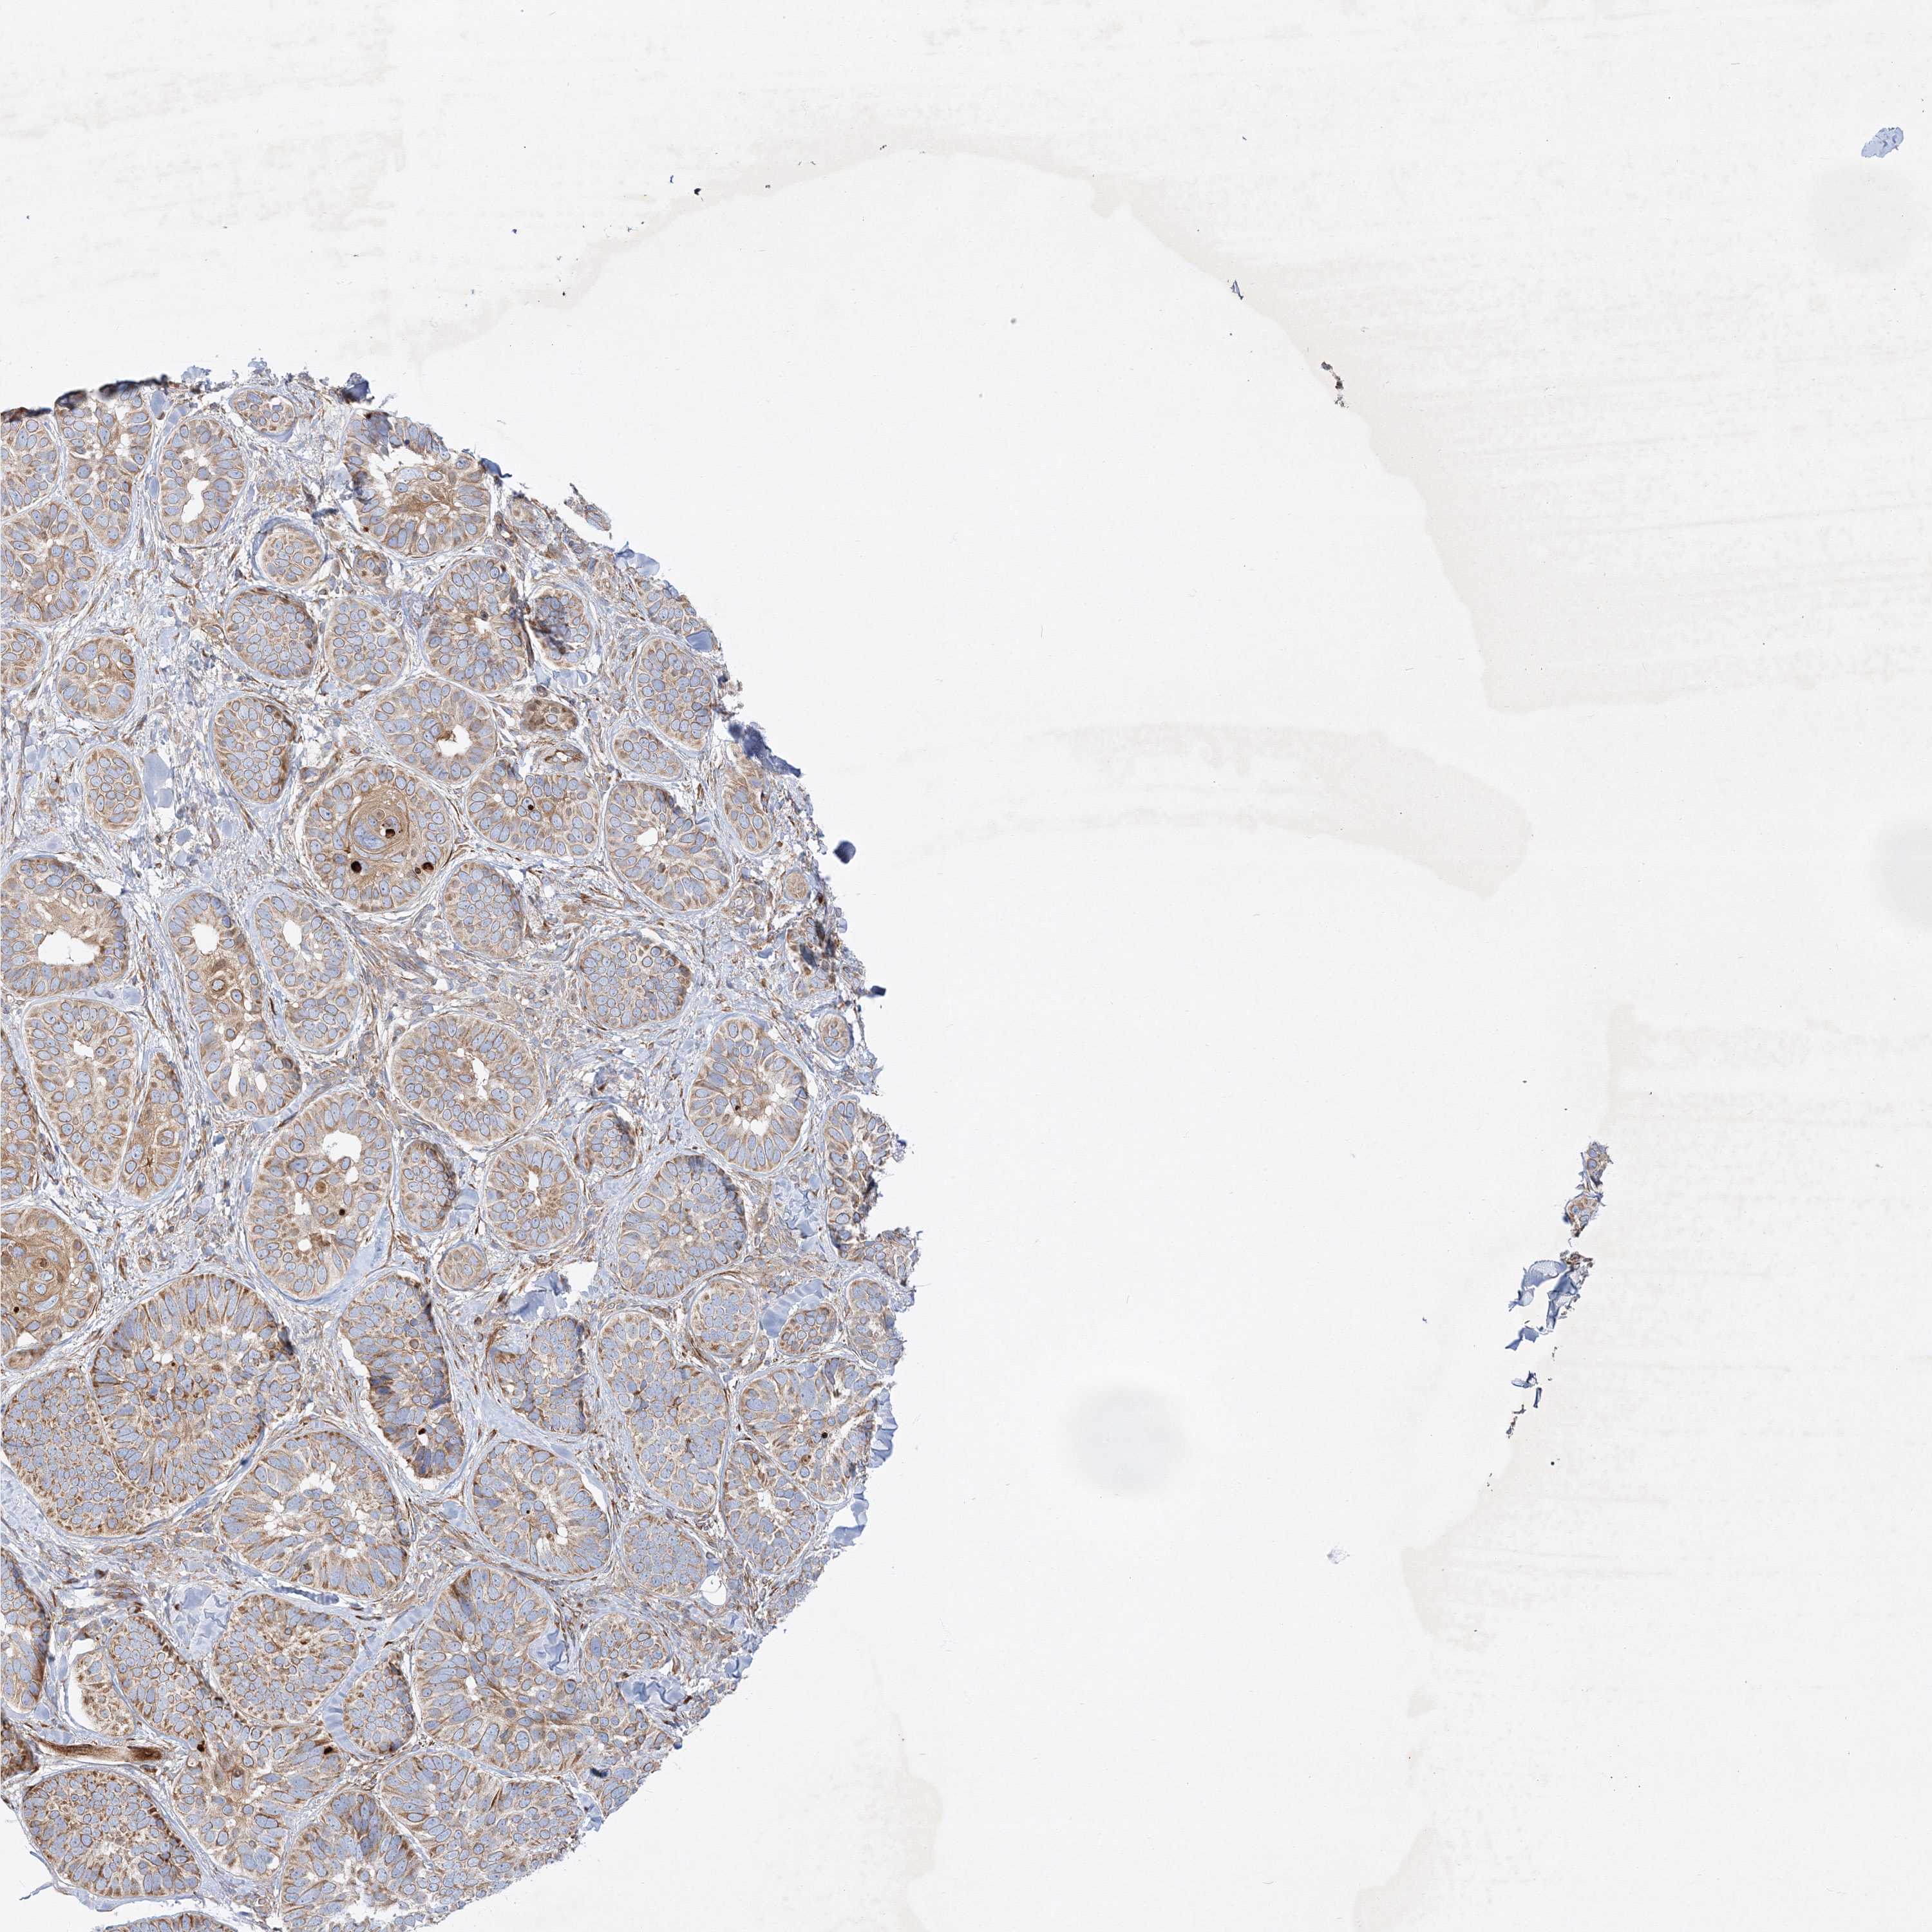

SKIN CANCER - Protein expressioni

A mouse-over function shows sample information and annotation data. Click on an image to view it in a full screen mode. Samples can be filtered based on level of antibody staining by selecting one or several of the following categories: high, medium, low and not detected. The assay and annotation is described here.

Antibody staining in the annotated cell types in the current human tissue is reported as not detected, low, medium, or high, based on conventional immunohistochemistry profiling in selected tissues. This score is based on the combination of the staining intensity and fraction of stained cells.

Each image is clickable and will lead to virtual microscopy that enables deeper exploration of all samples and also displays staining intensity scores, fraction scores and subcellular localization as well as patient and tissue information for each sample.

Antibody HPA035936

Squamous cell carcinoma, NOS